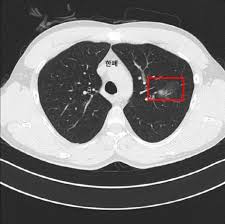

폐결절(pulmonary nodule)은 폐 안에 지름 3cm 이하의 작은 덩어리나 불투명 부위로, 흉부 X‑선이나 CT 검사에서 우연히 발견되는 경우가 많습니다. 대부분은 무증상이며, 양성인 경우가 많지만 일부는 악성(암)일 수 있어 주기적인 관찰이 필요합니다.

- 흉부 X‑선 또는 흉부 CT로 발견

- 결절 크기·형태·경계·석회화 여부 등 특징 분석